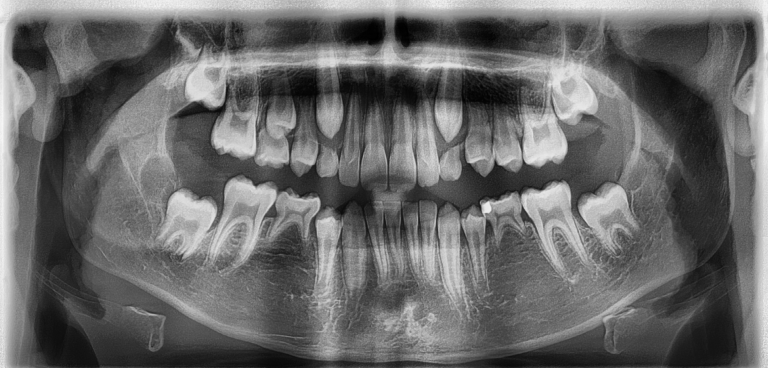

Das Panorama-Röntgen (Übersichtsaufnahme)

Dieses Bild ermöglicht uns eine umfassende Bewertung, die folgendes einschließt:

- die Struktur und Position der Zähne sowie den Zustand der Zahnwurzeln

- die Verfassung der Kiefergelenke

- die Beschaffenheit der Nasennebenhöhlen

- die allgemeine Qualität des Knochengewebes

- die Anordnung der Zähne zueinander

Häufig unter den Bezeichnungen Panoramaschichtaufnahme oder Orthopantomogramm (PSA / OPG / OPTG) geführt, bietet diese Aufnahme eine detaillierte zweidimensionale Ansicht des gesamten Kiefers in einer flachen Ebene. Diese Art von Röntgenbild nutz übrigens auch Ihr Zahnarzt. Informieren Sie uns gerne, wenn bereits eine Aufnahme erstellt wurde, diese können wir uns gerne anfordern.

Warum Panoramoröntgen?

Bei Kindern und Jugendlichen ist es wichtig zu wissen, ob alle bleibenden Zähne einschließlich der Weisheitszähne angelegt sind. Das Bild zeigt auch, ob die Zähne genug Platz haben, um durchzubrechen und wie weit die Zähne schon entwickelt sind. Das hilft uns zu beurteilen, wann der richtige Zeitpunkt für den Behandlungsbeginn ist.

Die Panoramaaufnahme gibt aber auch Hinweise auf mögliche Schwierigkeiten bei der Behandlung: Fehlende, zusätzliche oder verlagerte Zähne sind zu beachten. Außerdem ist anhand der Aufnahme eine Wurzelresorption, also ein Abbau der Zahnwurzel, erkennbar. Und wir bekommen einen Überblick über Füllungen, Kronen, Brücken, Implantate sowie Karies.